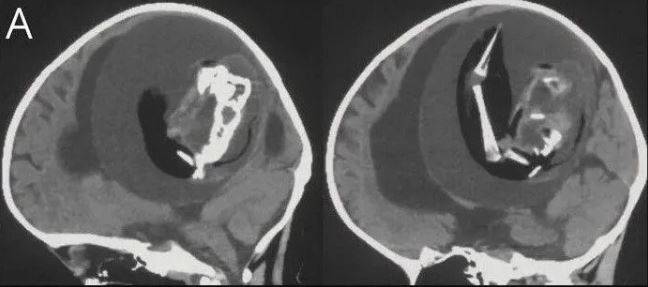

Körpənin kəllə sümüyünün gözlənildiyindən daha geniş olduğu və hərəkət problemi olduğu üçün xəstəxanaya gətirildiyi bildirilib. Hərəkət bacarıqları; iməkləmə, ayaqda durma, yerimə, qaçma, yellənmə, dönmə, yuvarlanma, atlama və tarazlıq kimi hərəkətləri təmin edir. Körpənin kəllə sümüyünü müxtəlif görüntüləmə üsulları ilə araşdıran tədqiqatçılar onun beyninin sıxıldığını və maye yığıldığını aşkar ediblər.

Əlavə müayinə nəticəsində məlum oldu ki, körpə hələ ana bətnində olarkən əkizi olub, lakin ikinci körpə kifayət qədər inkişaf edə bilməyib və körpənin kəllə sümüyünün içərisində ilişib qalıb.

Nəticədə kifayət qədər inkişaf etməyən bu embrion digəri tərəfindən saxlanılıb. Əməliyyatdan sonra bir yaşlı qızın vəziyyətinin necə irəlilədiyi barədə məlumat verilməyib.